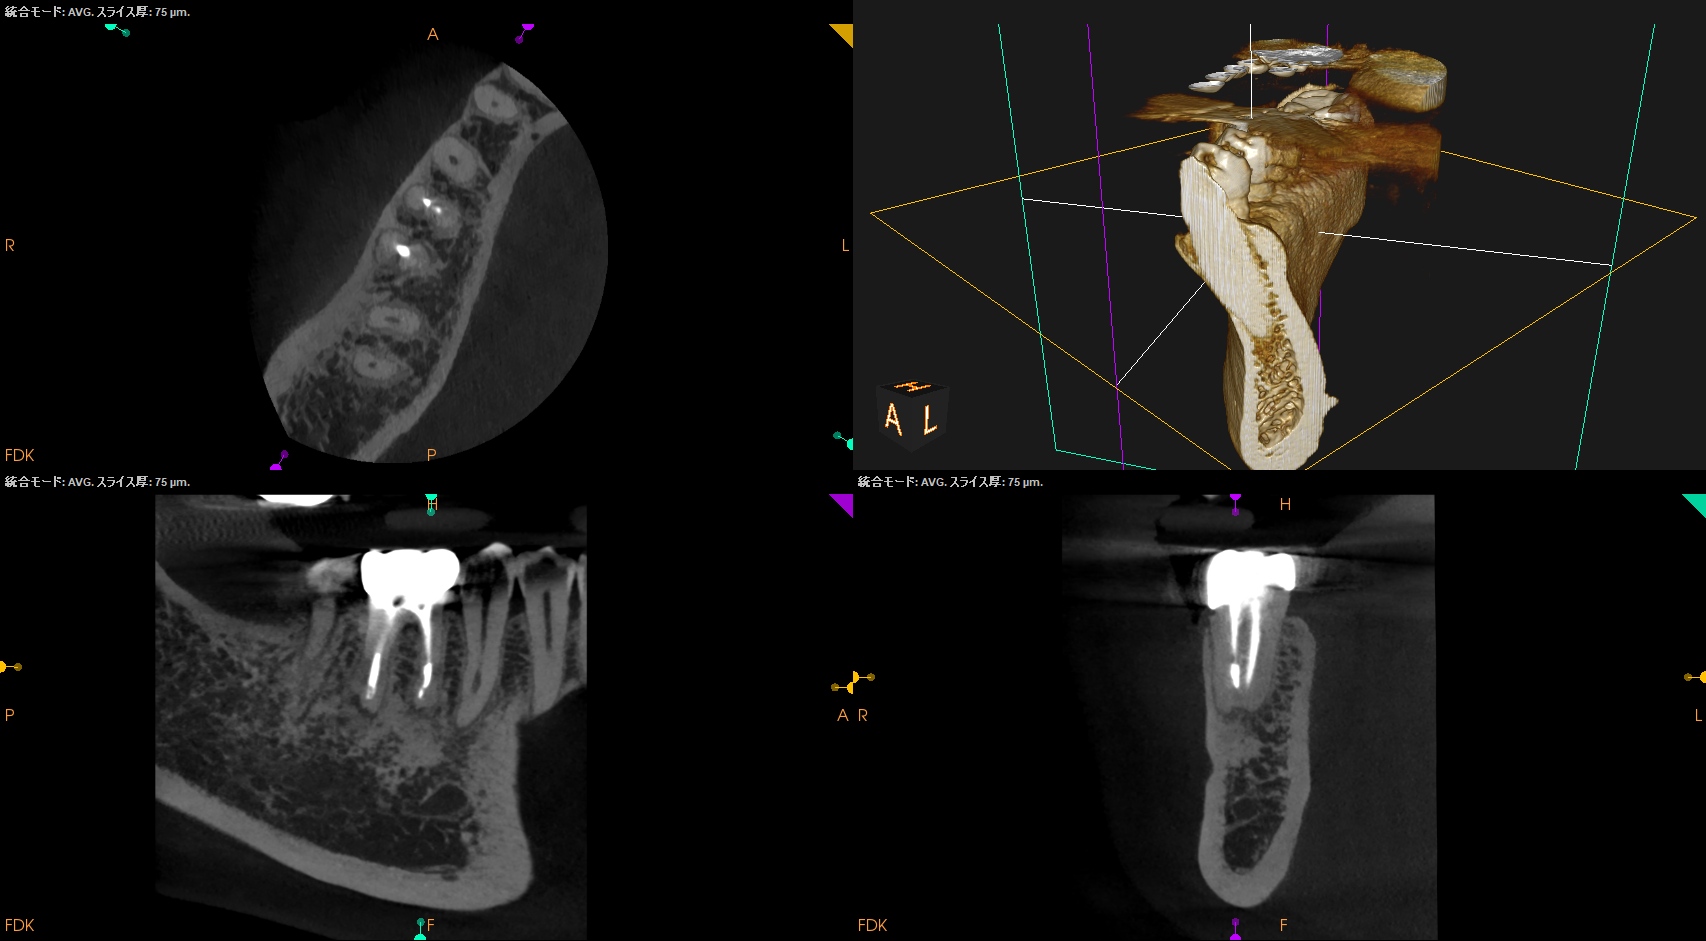

CBCT(2025.8.29)

#31

MB

ML

MBとML,どちらがストレートか?と言えばMLの方だろう。

MLをメイン根管にしてMBはそこに合流するという風に形成・根充すべきだろう。

D